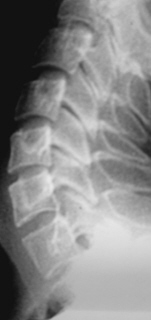

Иллюстрация 4. Определяется выраженная «выпрямленность» шейного лордоза. Имеет место скошенность передне-верхних лимбусов тел С3, С4, С5, С6. Определяется некоторое снижение высоты тела С 5 в передних отделах. В дугоотросчатых суставах определяется субхондральный склероз, неровность замыкательных пластинок.